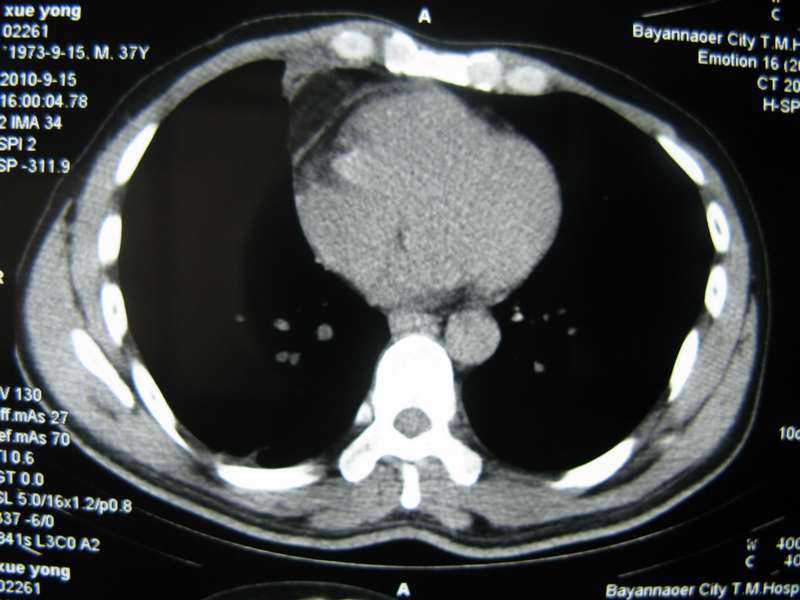

男,37岁,主述胸疼厉害,无咳嗽,无发热,血象也不高,病灶内ct值脂肪密度,右侧胸腔内少量积液,同道们考虑什么?谢谢!

脂肪垫,右下肺感染,少许积液是症状所在

纵膈脂肪堆积,右肺慢性炎症。

两肺下叶基底段纤维灶,右肺下叶基底背侧相应胸膜肥厚,右肺中叶内侧段部分不张。前中下纵隔团块状脂肪影,随访除外胸腺脂肪瘤。

不除外膈疝。